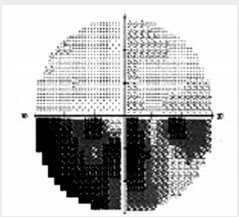

Выполнены общеклинические и офтальмологические исследования, статическая периметрия (см. рис. 3).

Результаты . На основании характерных жалоб, возраста, осмотра пациента, возникших поражений органа зрения, результатов проведенных офтальмологических исследований, данных МРТ, заключений консультантов, показателей анализа крови на гормоны выставлен диагноз: макроаденома гипофиза (гормононеактивная) с интрасупраселлярным ростом; хиазмальный синдром; нарушение кровообращения в ДЗН ОS вторичного генеза; миопия слабой степени ОD. Сопутствующий: АГ 2, риск 3.